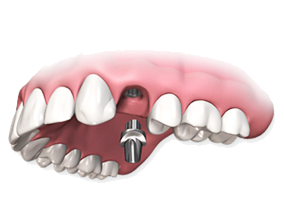

Восстановление челюсти на 4-х

или 6-ти имплантатах

Протезирование при полной адентии

Все на четырех или шести имплантах (all on 4 / all on 6)

Восстановление зубов по технологии All on 4 занимает один день. Потребуется внимательно изучить состояние костной ткани и выбрать места для установки 4 имплантатов на которых в тот-же день установят временную челюсть.

Постоянная челюсть фиксируется на имплантаты через 4-6 месяцев, после полного сращивания их с костью.